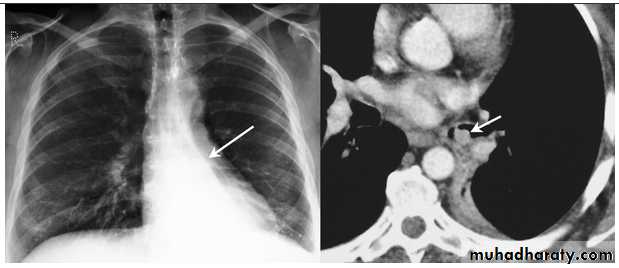

Thymoma.

A chest x-ray (A) reveals an unusual contour over the left hilum (arrows). That the hilum is not obscured (no silhouette sign) indicates that the mass must either be in front of or behind the hilum. A computed tomography scan (B) reveals a soft tissue mass (arrow) just to the left of the aorta. This is the most common location of a thymoma.